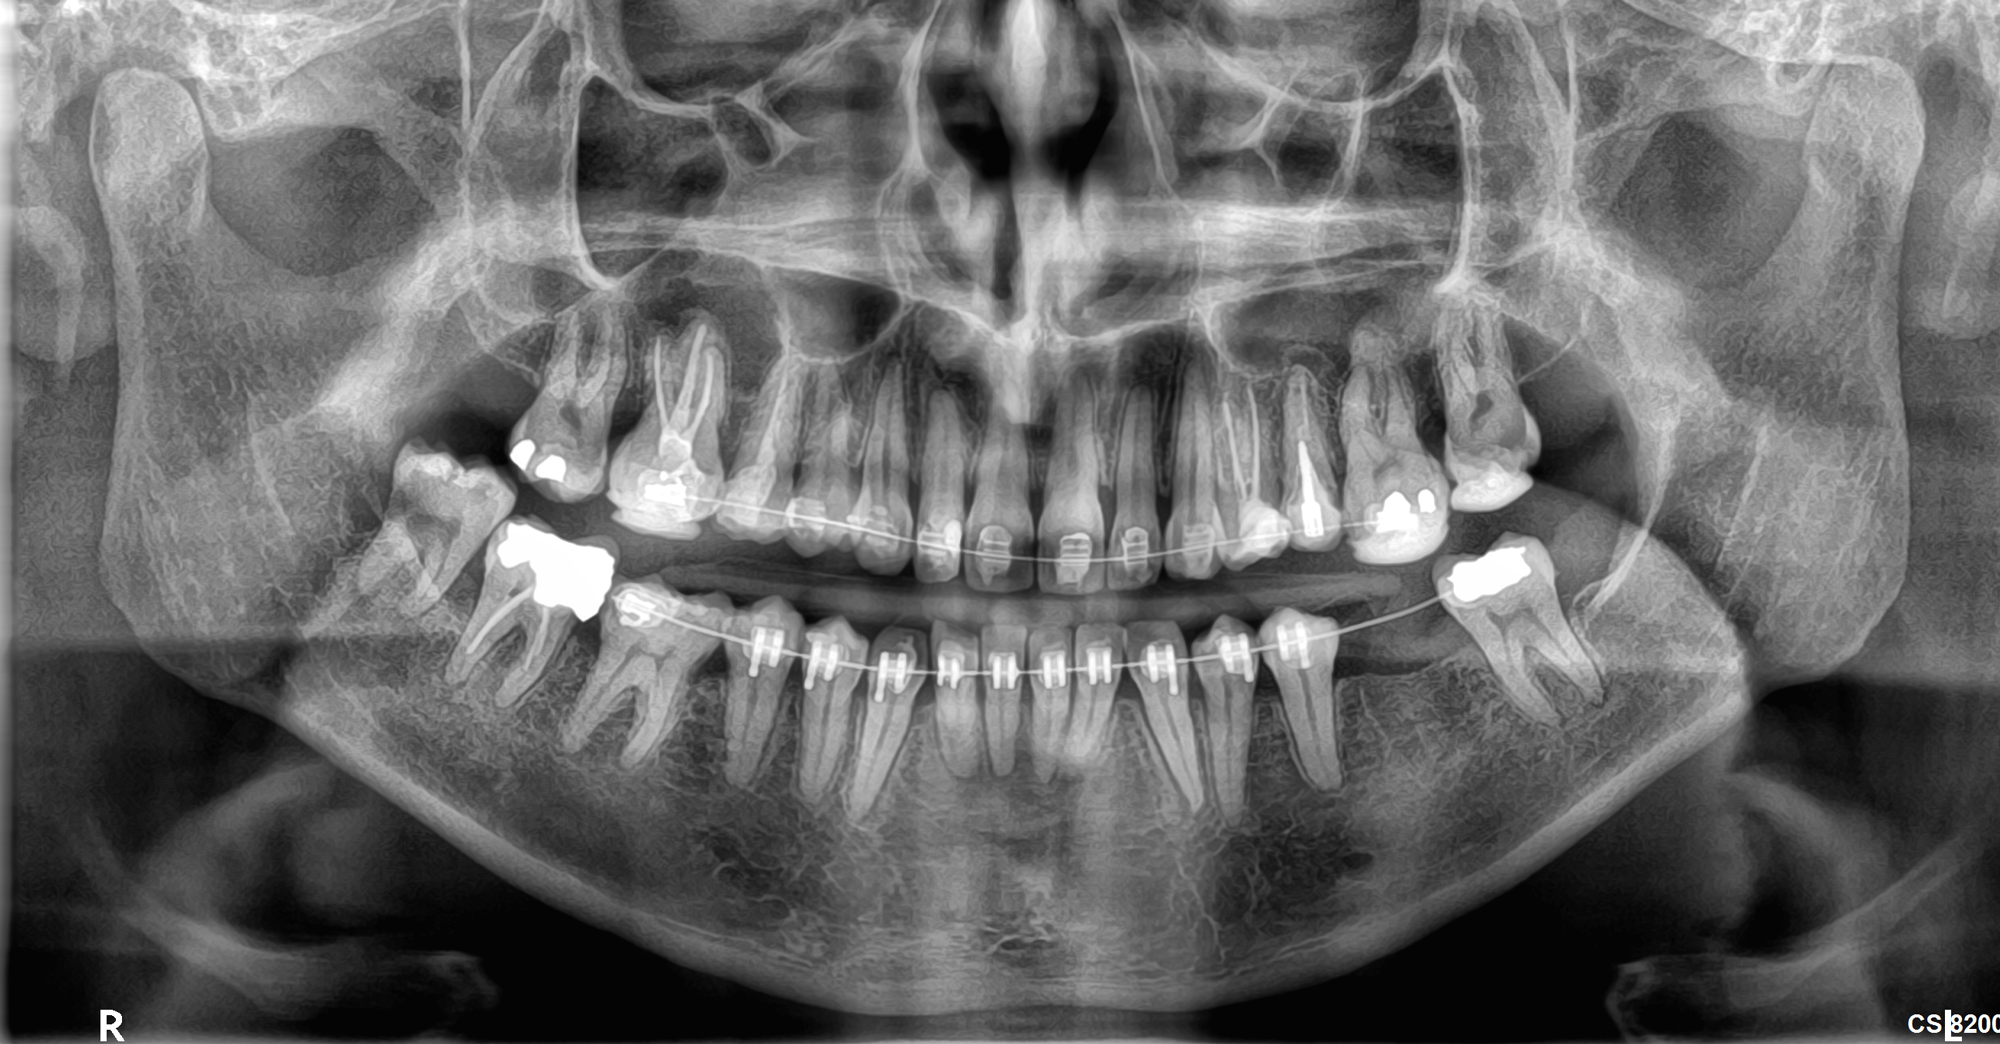

Το νέο μοντέλο CS 8200 3D Neo Edition της Carestream Dental συνδυάζει Ψηφιακή Πανοραμική με Ογκομετρικό Τομογράφο CBCT, με επιλογή εννέα οπτικών πεδίων και ανάλυση έως 75μm.

Με νέο εύχρηστο λογισμικό και ακόμα μεγαλύτερες δυνατότητες όπως το CS MAR, αλγόριθμος NAR, ανατομικά φίλτρα Endo, Perio,τεχνολογία Tomosharp, το καθιστούν ως το πιο κατάλληλο μηχάνημα για Οδοντιατρεία και Διαγνωστικά κέντρα καλύπτοντας όλο το φάσμα των απεικονίσεως οδοντογναθοπροσωπικής περιοχής με πεντακάθαρες εικόνες.